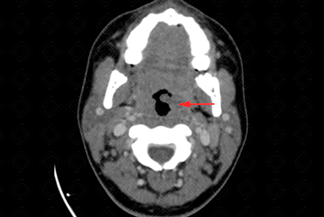

Texto alternativo para a imagem Figura 1. Créditos: Dra. Elazir Mota/ Rio de Janeiro - RJ

Descrição das figuras 1 e 2: Tomografia computadorizada de pescoço após a injeção do meio de contraste. Imagens axial e sagital evidenciando aumento de volume da região peritonsilar à esquerda, com impregnação heterogênea, caracterizando pequena coleção deste lado (setas vermelhas), medindo cerca de 2,0 x 1,5 cm, reduzindo discretamente a coluna aérea faríngea.